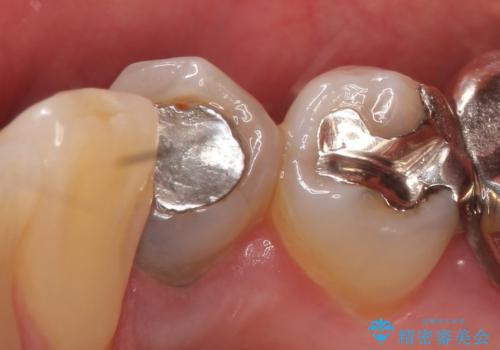

- 他院にて右下4番目の歯の再根管治療が必要だと言われた方の症例です。

再根管治療終了後、オールセラミッククラウンによる補綴を行いました。